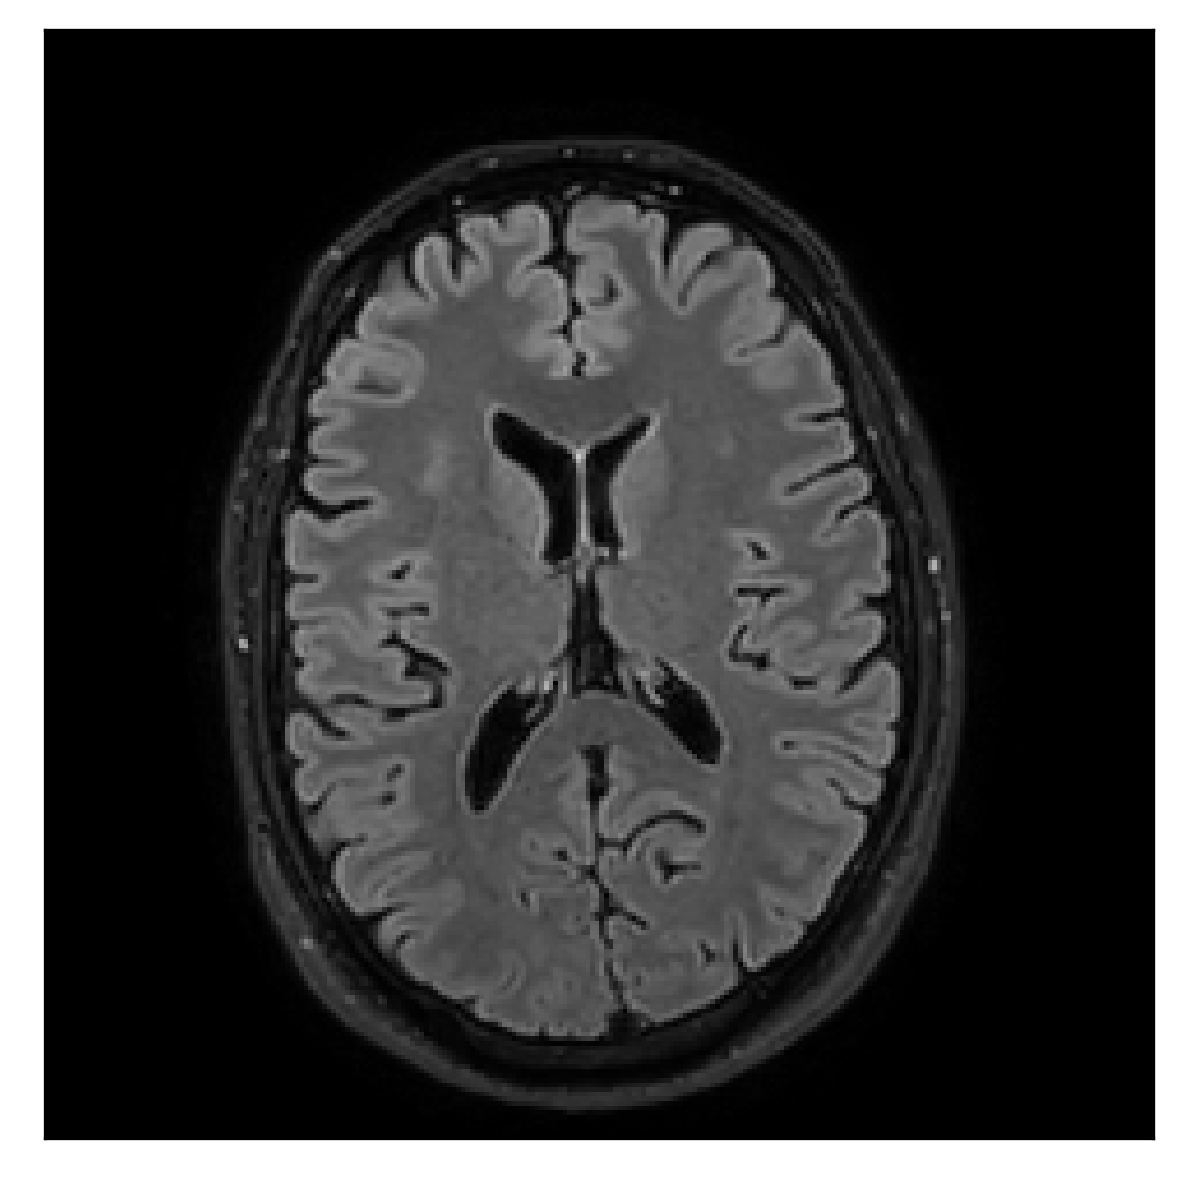

With the experiment described in Section 3.2, we demonstrate the flexibility of the correction scheme with respect to the choice of the reference contrast. The results are shown in Figure 10. Contrary to the experiments detailed in the previous section, we are now considering a T2-weighted reference contrast to guide the correction of a T1-weighted corrupted contrast. The quality of the correction indicates that the proposed technique is rather flexible in terms of reference contrast.

| Section 3.2, Figure 10 | Sagittal | 25.84 | 28.07 | 0.7032 | 0.8093 |

| Coronal | 26.35 | 30.40 | 0.7851 | 0.9021 | |

| Axial | 28.11 | 30.54 | 0.8248 | 0.9012 | |

| Section 3.2, Figure 10 | T1 | Completely corrected | Some blurring | No additional artifacts | Good grey white matter differentiation, |

| some loss of grey matter low signal | |||||